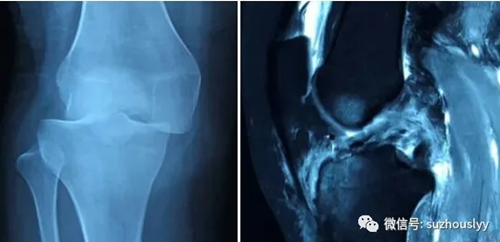

患者骑电瓶车摔伤致膝关节肿痛伴活动受限,急诊到医院拍摄膝关节X线提示膝关节脱位,膝关节MRI提示膝关节前后交叉韧带断裂;我院骨一科关节镜团队接诊后,即可诊断出患者膝关节前、后交叉韧带断裂,需行关节镜手术治疗;关节镜进入关节腔后,发现前后交叉韧带已完全断裂;经过两个半小时的手术,关节镜团队成功为患者重建两条韧带。

我院骨一科科主任刘长征谈到膝关节外伤常导致膝关节前交叉韧带断裂或膝关节后交叉韧带断裂;而膝关节前、后交叉韧带同时断裂十分少见,手术步骤十分复杂,手术耗时较长,是对手术团队的巨大考验,而全镜下韧带重建手术极大的减轻手术创伤,有利于患者术后更快更好的康复!